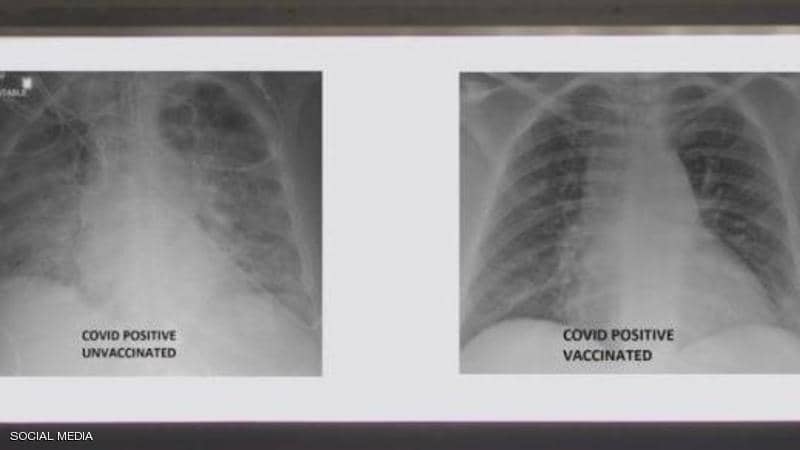

صور أشعة توضح الفرق بين رئتي شخص مطعم ضد كورونا وآخر غير محصن

نشر الطبيب العربي في الولايات المتحدة، غسان كمال، صورة تظهر الفرق بين رئتي شخص جرى تطعيمه ضد فيروس كورونا ورئتي شخص آخر لم يتلق التطعيم، مشيرا إلى أن الاثنين أصيبا بفيروس كورونا.

وأظهرت صور الأشعة السينية، أن رئتي الشخص غير الملقح، المصاب بفيروس كورونا كانت بيضاء بصورة شبه كاملة وتعرف بـ"عتامة الرئة"، مما يعني أنها كانت غارقة في الفيروس، في حين أبرز صور رئتي الشخص ببيضاء أقل.

وتعني صورة الأول أيضا نقصا في دخول الهواء إلى رئتيه، فيما تعني لدى الثاني أن الهواء يتدفق بسهولة علاوة على أن رئتيه خاليتين من الوباء.

آثار لقاح كورونا في رئتي الشخص

وأشار إلى أنه نشر الصور من أجل إظهار الفرق الذي يمكن أن يحدثه اللقاح في رئتي الشخص في حال إصابته بالفيروس، وهذا حتى يتعرف الجميع على الآثار التي تظهر على الرئة نتيجة اللقاح.